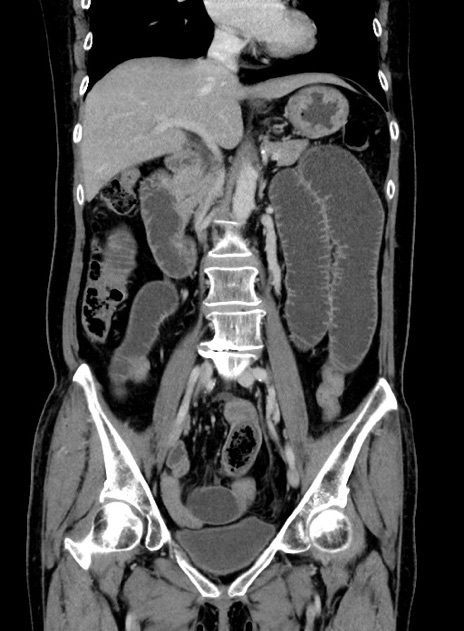

症例9(冠状断像)

【症例】 60歳代女性

【主訴】むかつき、みぞおちの痛み

【現病歴】3日前よりむかつきがあり、食事がとれない。

【既往歴】糖尿病

【身体所見】発熱なし、心窩部圧痛軽度あるも、腹膜刺激症状なし。

【データ】WBC 7400、CRP 1.92